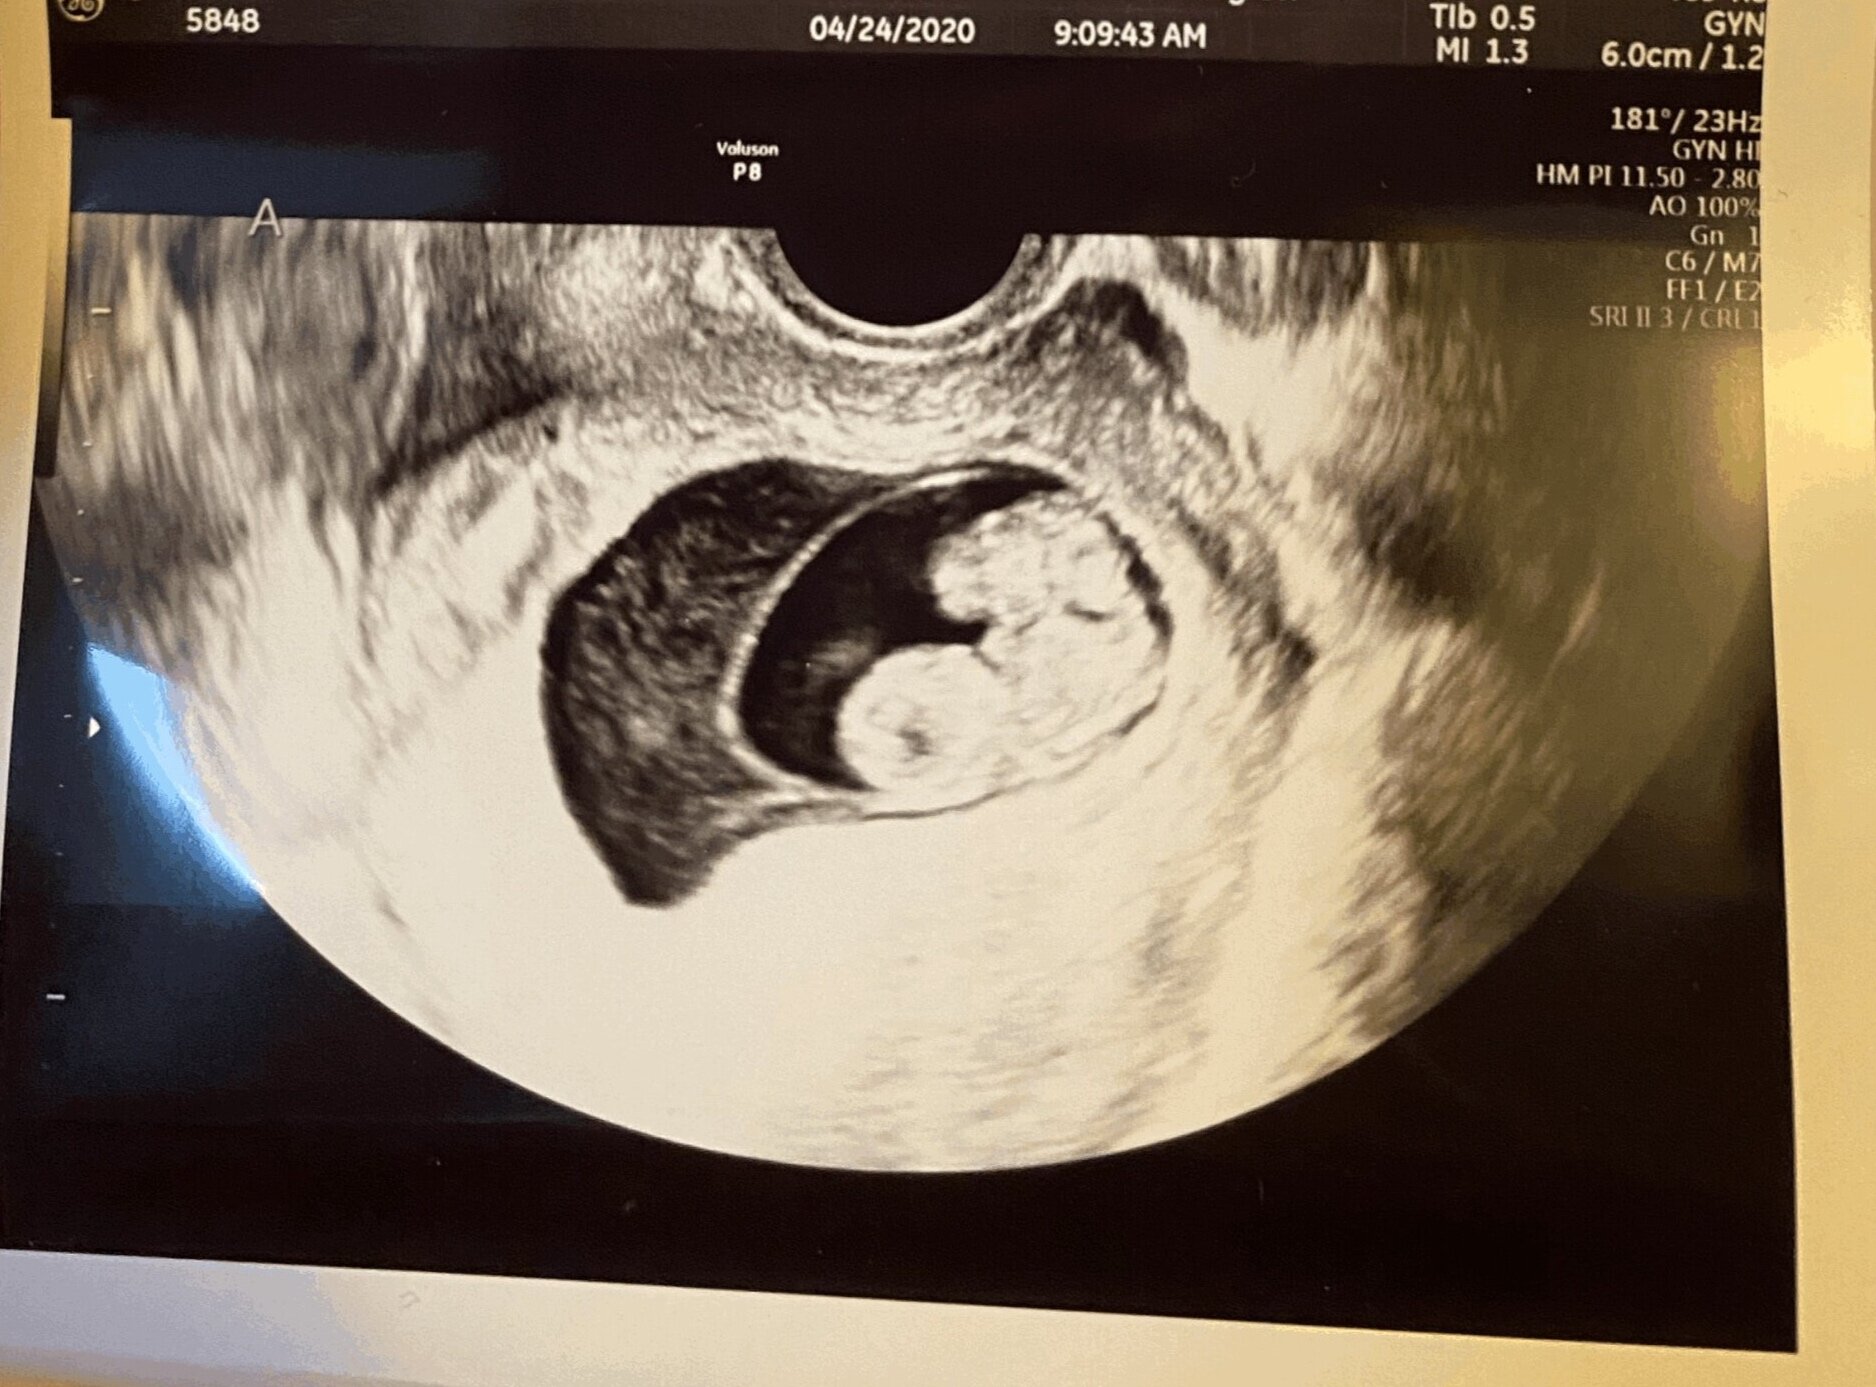

We were not aware I was carrying twins until 8 weeks in, a second ultrasounds showing two little heartbeats flickering away. Like so many other women at this time, I was attending all my appointments alone as the pandemic put a stop to partners attending such events. I was initially congratulated but the joy of seeing such a sight was quickly tarnished as my sonographer said she couldn’t see a separating membrane between the two babies. The first of many, many blows. I was referred to Maternal Fetal Medicine for a clearer diagnosis with a follow up scan booked for the following week.

I was carrying Monoamniotic twins, a rare and extremely high risk pregnancy with, mostly, negative outcomes. The twins were to share both a placenta and just one amniotic sac; giving way the inevitable outcome of entangled umbilical cords which could at any moment end their journey earthside. My husband was brought into the conversation with the OBGYN via Zoom to discuss our options, one being to terminate the pregnancy as the chances of them making it was slim. We were given 24 hours to make a decision. We discussed the various outcomes, we cried and we asked why us. I never had a moments doubt that I would continue the pregnancy.